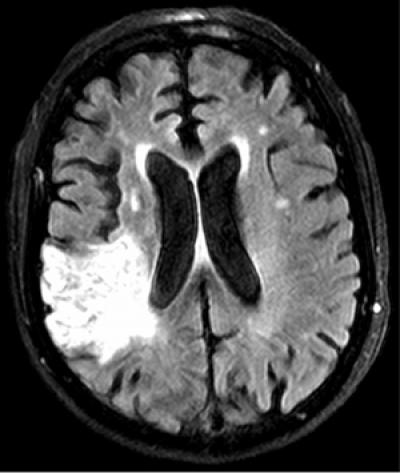

image: Physicians have sharply reduced stroke treatment time by applying a process for improving efficiency originally developed by carmakers. Early treatment helps prevent or reduce brain damage, shown in white in the scan. view more

Beginning stroke treatment earlier can help prevent the brain damage that causes paralysis and loss of speech after a stroke. The researchers say the drop in treatment time results from applying a key component of lean manufacturing to patient care: getting input from all members of the team to identify inefficient steps involved in the process.